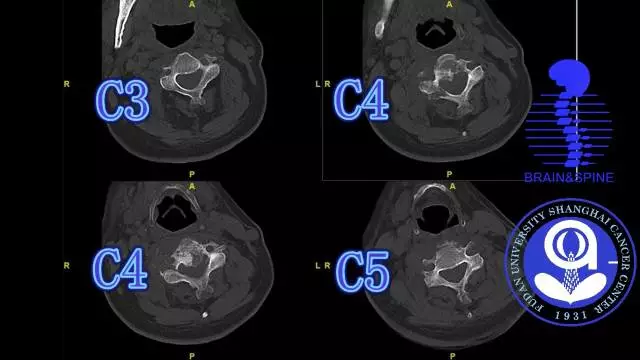

手术过程